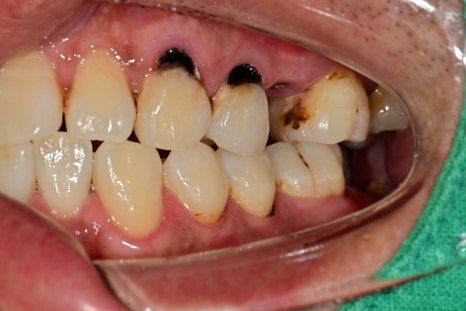

엑스레이, 구강 내 사진을 보게 되면 여러 종류의 치료가 필요한 부위들이 보입니다

충치로 인한 심미적인 부분, 치아 상실 부위, 대합 치아가 없다 보니 아래로 내려온 치아,

깊은 충치로 인한 신경치료가 필요한 치아까지

좌우 다수의 치아에서 치료가 필요했습니다.

앞니 쪽의 새까맣던 충치 부위도 치아색에 맞춰서 레진 치료까지 마무리되었습니다

범위가 너무 넓으면 크라운치료가 필요한 경우가 있지만

레진으로도 충분히 치료가 가능해 보였기 때문에

최대한 치아색에 맞춰서 치료를 했습니다.